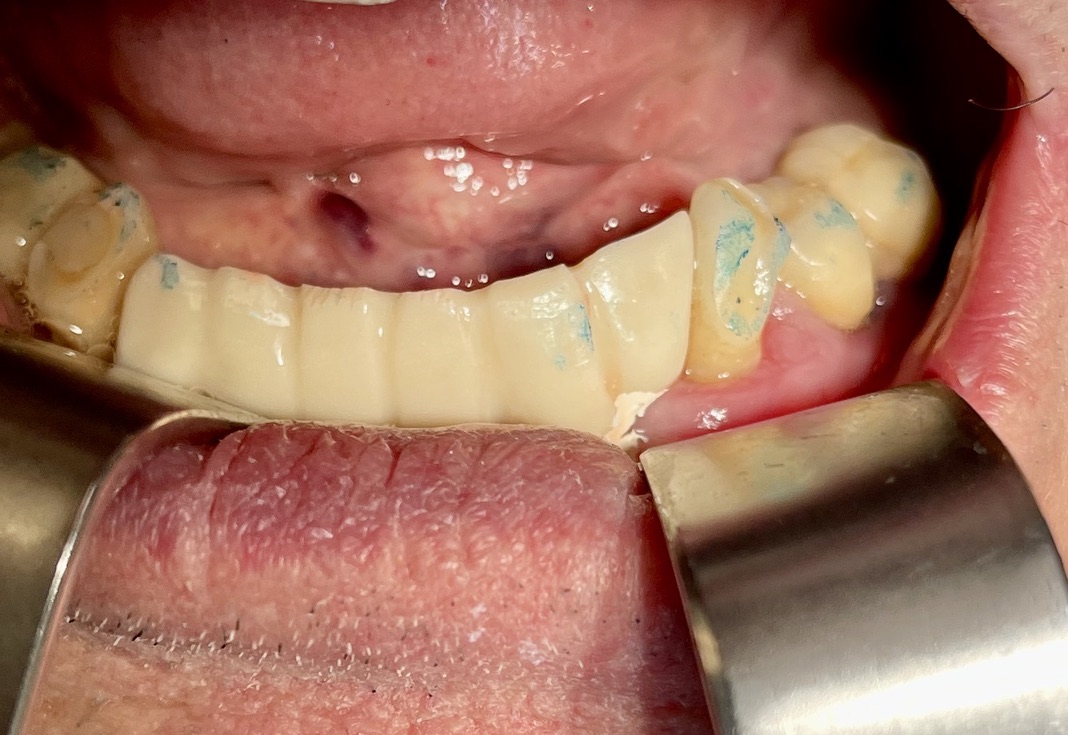

CLINICAL CASE combined with news n.6. Rehabilitation of 04/28/2021

In particular, I consider the following aspects to be significant:

• 1 Age of the patient: 83 years old

• 2 Execution of the first 6 plants: 25 years ago.

• 3 Execution of the 5 subsequent plants: 14 years ago

• 4 Medicines taken by the patient: none

• 5 Presence of implants in the tuber / pterygoid area

• 6 Presence of ancient inclined implants

• 7 Presence of implant bent in 25. (To parallelize it)

• 8 Presence of two mini-plants in 11-12

• 9 Presence of a welded bar in the upper sector

• 10 Severe periodontal disease of the lower sector

• 11 Hygiene issues

• 12 Implant failure of lower Tramonte implant, implant prior to 2004, in the context of general periodontal disease

• 13 The insertion of the three implants did not involve bone or connective tissue grafts

• 14 It did not make detachments necessary

• 15 It was not necessary to isolate the emergencies of the inferior alveolar nerves

• 16 Since we are dealing with high-density bone, we resorted to the helical drill, an instrument rarely used by us because it is not necessary and because there are areas where its use involves surgical risks that are not acceptable to us. In addition, this drill removes discrete amounts of bone that we prefer to remain where nature has put it. It is interesting that the diameter of the cutter is only 2 mm

• 17 Being dense bone, the implants used had a diameter of only 4 mm after tapping with the corresponding tap

• 18 At the check-up on 3/5/2021 the patient is not swollen and reports that he is finally eating well

• 19 Implant surgery starts at 8.45am. end of implant surgery at 9.36

• 20 Cementation of the provisional, packaged at the moment, completed at 10.30. total length of stay of the patient in the clinic 1.45 hours.

The images provide additional information in the captions.